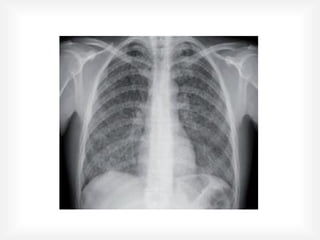

El documento habla sobre la tuberculosis pulmonar causada por el bacilo Mycobacterium tuberculosis. Explica las características del bacilo, la epidemiología global y nacional de la enfermedad, las vías de transmisión y las opciones de evolución al exponerse al bacilo. También cubre el diagnóstico, tratamiento y complicaciones de la tuberculosis pulmonar, así como los fármacos utilizados para el tratamiento.